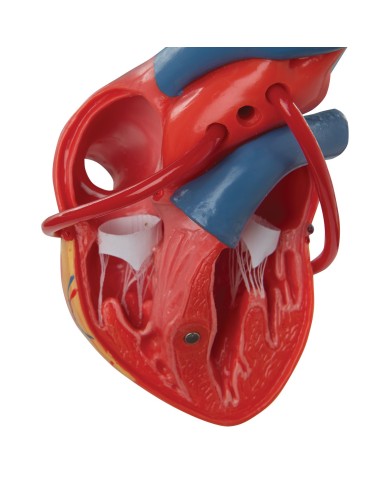

Modello di cuore di alta qualità scomponibile in 5 parti

Modello di cuore di alta qualità scomponibile in 5 parti

La parete anteriore del cuore è staccabile per poter vedere i ventricoli.